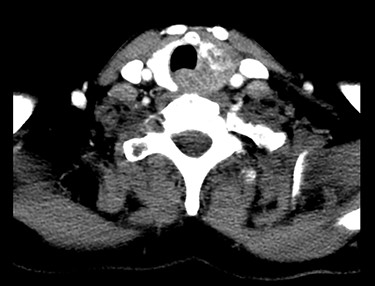

In late August 2018 she reported worsening hoarseness and US showed an enlarged left thyroid lobe with pseudonodular formations. Fine needle aspiration cytology showed poorly differentiated basaloid cells, Bcl2+, CD117+, TTF1−, thyreoglobulin−, chromogranin−, consistent with ACC localization. A restaging CT showed an inhomogeneous alteration of the left thyroid lobe without lateral cervical significant lymphadenopathies (Fig. 2). Brain CT was negative for metastatic localization. The upper airway evaluation revealed a fixity of the left hemilarynx.

Chest CT showing an inhomogeneous alteration of the left thyroid lobe, corresponding to the metastatic thyroid involvement from the ACC.